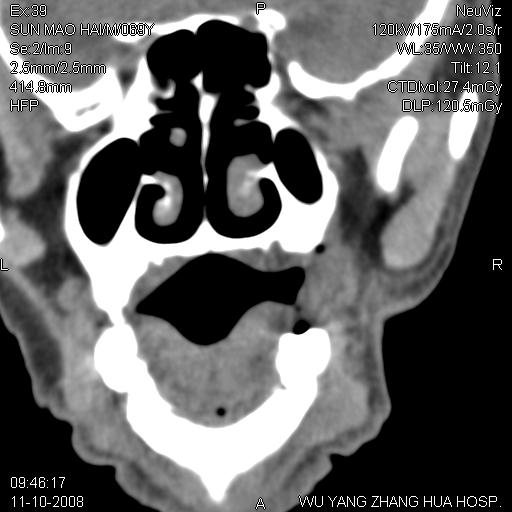

标题: CT16568:右面部瘘管半年余,无其它不适.

考虑右上颌异位齿(或斜向阻生齿)并根尖脓肿。

1.右上颌异位齿

2.右上颌化脓性骨髓炎

3.右下鼻甲肥大